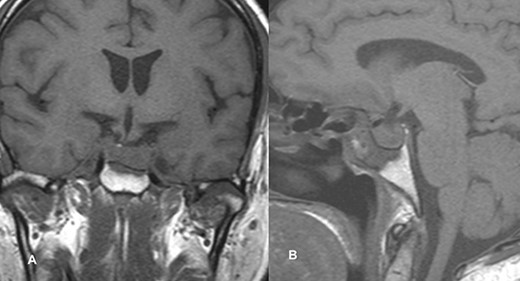

MRI imaging showed a 2 × 1.6 × 1.6 cm sized sellar lesion arising from the pituitary fossa with an intrinsic high T1 signal in the periphery, extending superiorly in the suprasellar region and laterally, causing a mass effect on the left cavernous sinus. A signal void was seen in T2-weighted images suggestive of hemorrhage (Fig. 3).

MRI images of post-contrast sagittal T1 (A), sagittal T1 (B), axial T2 (C), and post-contrast axial T1-weighted images (D) showing a 2 cm × 1.6 cm × 1.6 cm sized sellar lesion arising from the pituitary fossa extending superiorly in the suprasellar region and laterally causing a mass effect on the left cavernous sinus with intrinsic high T1 signal in the periphery and signal void on T2-weighted images suggestive of hemorrhage.